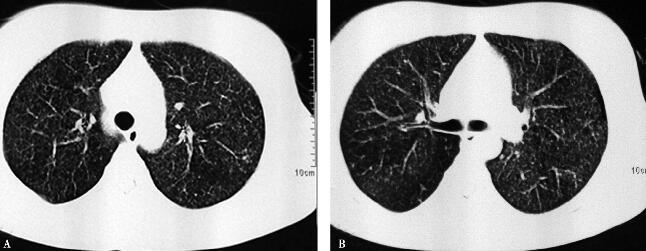

七、完善胸部CT的结果

胸部CT(图2)示双肺可见弥漫均匀分布的小粟粒状阴影。此时结合患者年轻、高热、用一般抗生素治疗无效,可诊断为急性血行播散型肺结核。但需注意,肺部的小粟粒状阴影应该与弥漫性泛细支气管炎、细支气管肺泡癌、粟粒型肺转移癌、间质性肺疾病等鉴别。脑脊液涂片抗酸染色可见结核菌。

图2

采用异烟肼、利福平、乙胺丁醇、吡嗪酰胺四联抗结核治疗。治疗1个月后,临床症状消失,胸部CT病灶明显吸收。